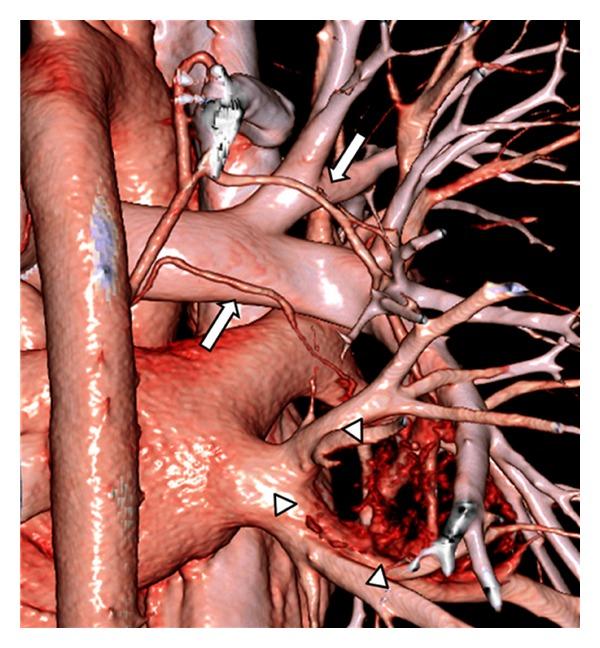

Castleman's disease is an uncommon lymphoproliferative disorder of unknown etiology, most often involving the mediastinum. It has 2 distinct clinical forms: unicentric and multicentric. Unicentric Castleman's disease arising from an intrapulmonary lymph node is rare, and establishing a preoperative diagnosis of this disease is very difficult mainly due to a lack of specific imaging features. We report a case of intrapulmonary unicentric Castleman's disease in an asymptomatic 19-year-old male patient who was accurately diagnosed by preoperative computed tomography (CT). The mass was incidentally found on a routine chest X-ray. A subsequent dynamic CT showed a well-defined, hypervascular, soft-tissue mass with small calcifications located in the perihilar area of the right lower lung. Three-dimensional CT (3D-CT) angiography indicated that the mass was receiving its blood supply through a vascular network at its surface that originated from 2 right bronchial arteries. The clinical history and CT findings were consistent with a diagnosis of unicentric Castleman's disease, and we safely and successfully removed the tumor via video-assisted thoracoscopic surgical lobectomy. This case shows that the imaging characteristics of these rare tumors on contrast-enhanced CT combined with 3D-CT angiography can be helpful in reliably establishing a correct preoperative diagnosis.

Castleman病是一种病因不明的罕见淋巴增生性疾病,最常累及纵隔。它有两种不同的临床形式:单中心型和多中心型。起源于肺内淋巴结的单中心型Castleman病很罕见,主要由于缺乏特异性影像学特征,术前诊断这种疾病非常困难。我们报告一例19岁无症状男性患者的肺内单中心型Castleman病,其通过术前计算机断层扫描(CT)被准确诊断。该肿块是在常规胸部X线检查时偶然发现的。随后的动态CT显示在右下肺门周围区域有一个边界清晰、血供丰富、有小钙化的软组织肿块。三维CT(3D-CT)血管造影显示该肿块通过其表面起源于2支右支气管动脉的血管网络获得血供。临床病史和CT表现与单中心型Castleman病的诊断相符,我们通过电视辅助胸腔镜手术肺叶切除术安全且成功地切除了肿瘤。该病例表明,这些罕见肿瘤在增强CT结合3D-CT血管造影上的影像学特征有助于可靠地建立正确的术前诊断。